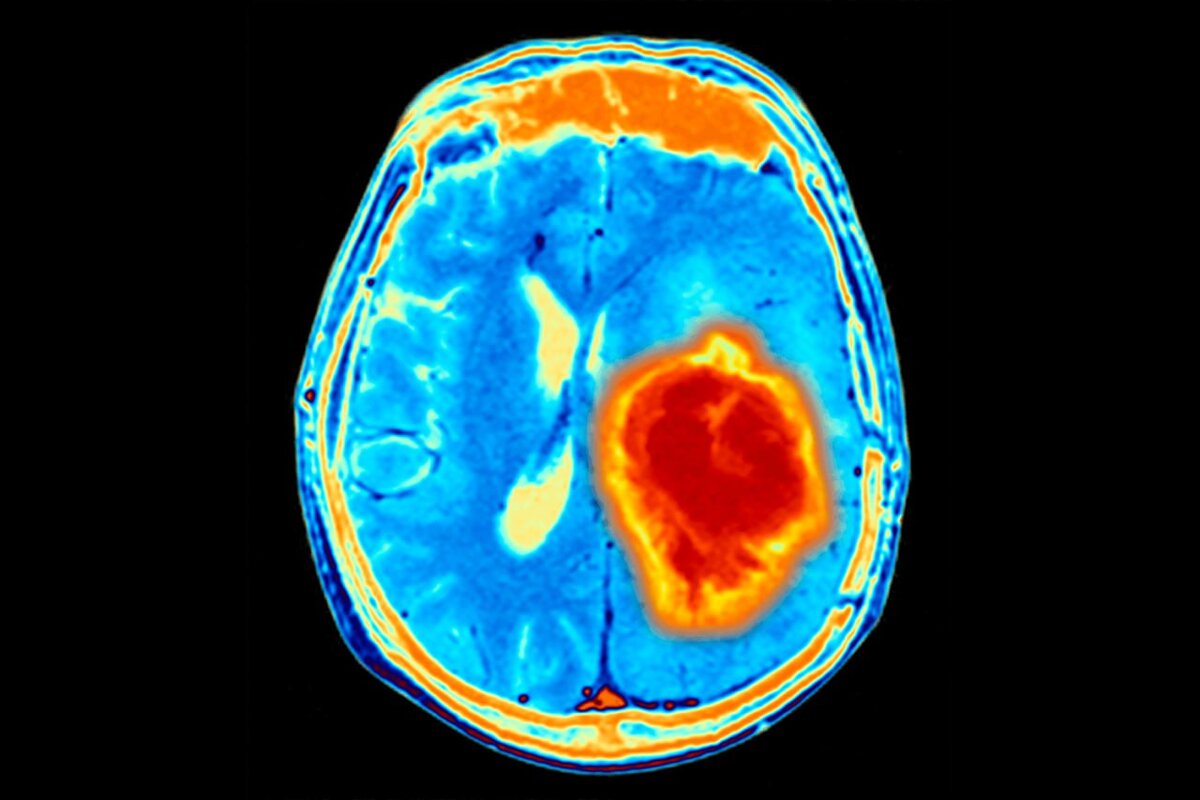

Прорыв в лечении Глиобластомы

Глиобластома — это агрессивный тип опухолей головного мозга с низкой степенью выживаемости у пациентов. Как правило, при таком типе заболевания показано хирургическое вмешательство, но не всегда хирургу удаётся удалить всю опухоль целиком. Резко повысить выживаемость пациентов со злокачественными опухолями мозга, возможно, смогут инженеры-химики из США благодаря новому подходу.

Свежая разработка с многообещающими результатами — гидрогель, который вводится в место локализации опухоли после её удаления.

В специальный раствор добавляются противоопухолевые лекарственные препараты и антитела. Такой препарат самостоятельно собирается в гидрогель и заполняет собой пространство, оставшееся после удаления опухоли, понемногу высвобождая действующие вещества, которые подавляют оставшиеся злокачественные клетки.

Удивительно не только то, что применение гидрогеля у мышей, больных глиобластомой, обеспечило 100% выживаемость, но и то, что при повторном заражении иммунная система самостоятельно справилась с опухолевыми клетками без какой-либо дополнительной терапии.